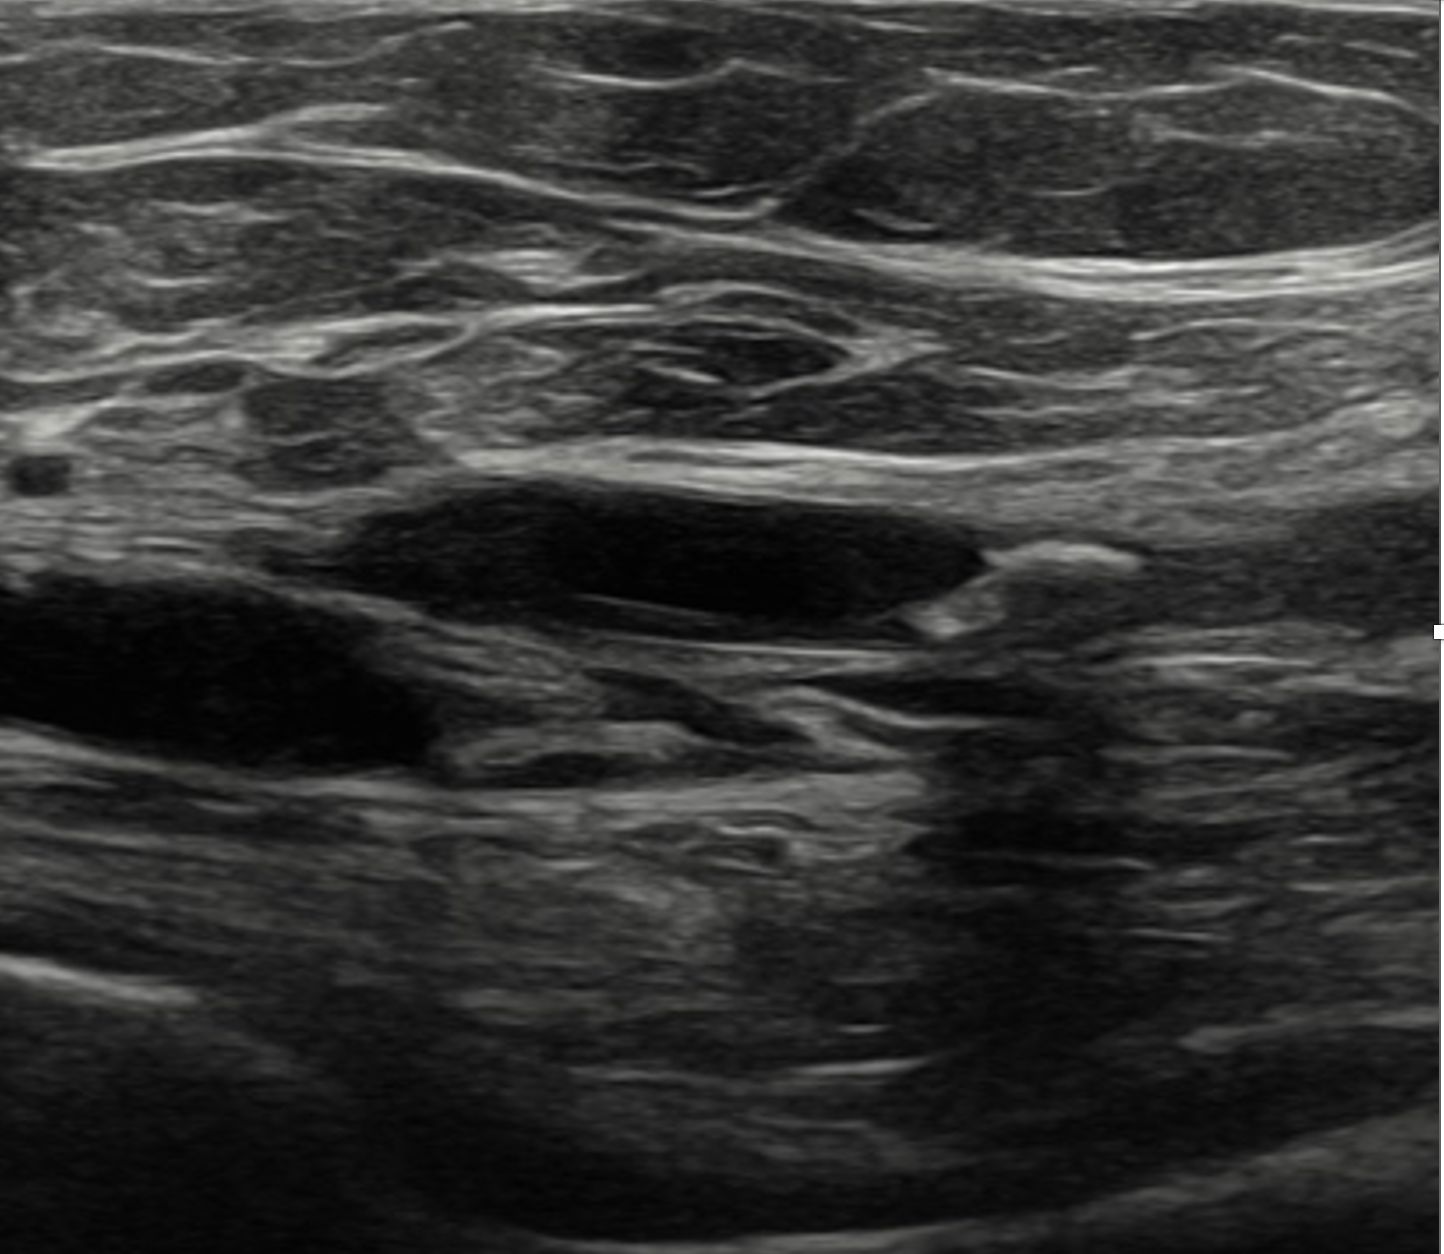

Dado el acceso a ecografía clínica en el centro de salud, se realiza la misma.

Hallazgos ecográficos

Se identifican placas de ateroma en ambas arterias femorales comunes, con pérdida del flujo diastólico, hallazgo sugestivo de enfermedad aterosclerótica significativa.